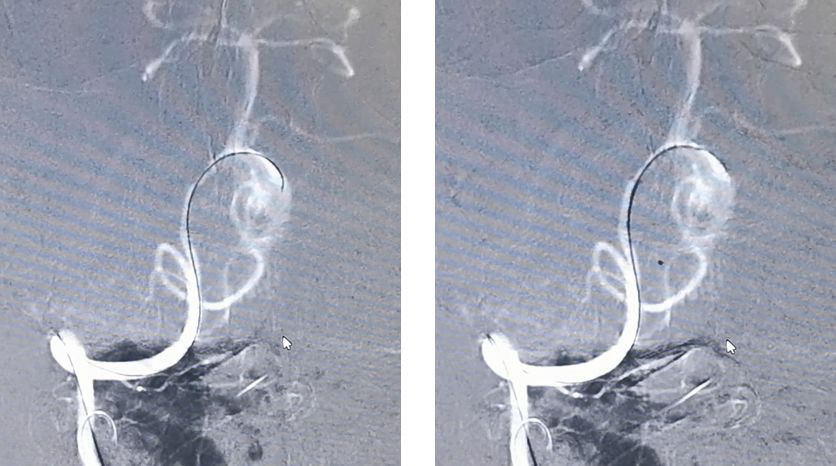

先用Synchro-200携Echelon-10由右椎动脉进入动脉瘤腔,微导管在瘤腔内盘圈,可以在输送弹簧圈的时候使弹簧圈分布更均匀

然后将Marksman微导管通过左侧椎动脉顺利进入左侧大脑后动脉

PED支架沿Marksman进入准备释放

释放PED。由于瘤颈很宽,所以PED需要足够长,动脉瘤远端和近端才能具有足够的锚定力量,防止支架坠入瘤腔内。所以,我们选择了3.25*35mm的支架。支架上端定位在基底动脉中段

PED释放完毕,位置及贴壁良好,左椎-基底动脉血运通畅,未填弹簧圈,即可见到瘤腔内造影剂的滞留,说明支架贴壁良好,起到了良好的重建作用